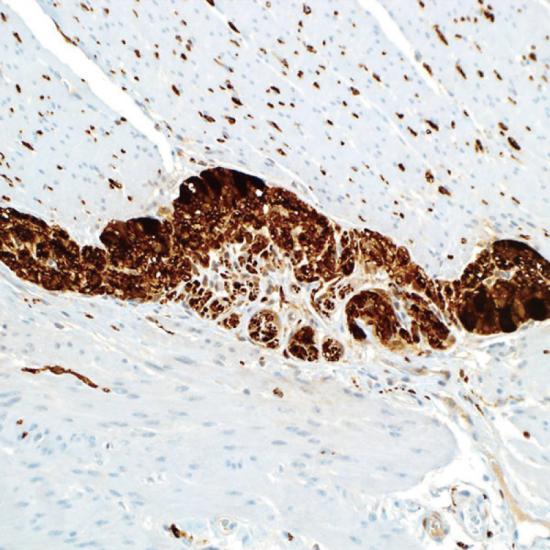

PGP9.5

Protein Gene Product 9.5抗體試劑(免疫組織化學(xué)) 閩廈械備20180215號

• 預(yù)處理:

熱修復(fù)

• 陽性部位:

細(xì)胞漿/細(xì)胞核

• 陽性對照:

神經(jīng)內(nèi)分泌腫瘤

蛋白基因產(chǎn)物9.5(PGP9.5)是一種神經(jīng)纖維中的特異性泛素羥基水解酶,作為一種神經(jīng)軸突標(biāo)記物,PGR9.5可以與任何無髓或有髓的神經(jīng)纖維相結(jié)合,使用免疫組織化學(xué)的方法即可標(biāo)記出組織中PGP9.5陽性的神經(jīng)纖維。目前PGP9.5主要應(yīng)用于周圍神經(jīng)損傷的臨床研究中。